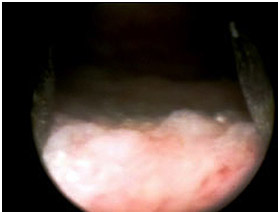

Плоскоклеточная метаплазия с участками кератинизации (лейкоплакия мочевого пузыря). Увеличение х 200, окраска гематоксилин-эозином.

Рим.2 Плоскоклеточная метаплазия с участками кератинизации (лейкоплакия мочевого пузыря). Увеличение х 200, окраска гематоксилин-эозином.